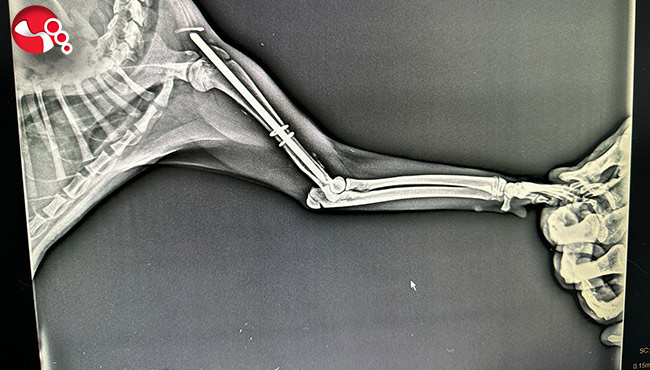

Edinilen bilgiye göre Terakki Mahallesi'nde aracın çarptığı sokak kedisini gören esnaflar kediyi alarak veteriner kliniğine getirdi. Burada yapılan ilk muayenesinde ön kol ve arka ayak kemiklerinde kırık olduğu tespit edilen kedi ameliyata alındı. Kedi ameliyatın ardından sağlığına kavuşacağı günü beklerken hayırsever vatandaşların çabası takdirle karşılandı. Kedinin ameliyat masrafları da hayırsever vatandaşlar tarafından karşılandı.